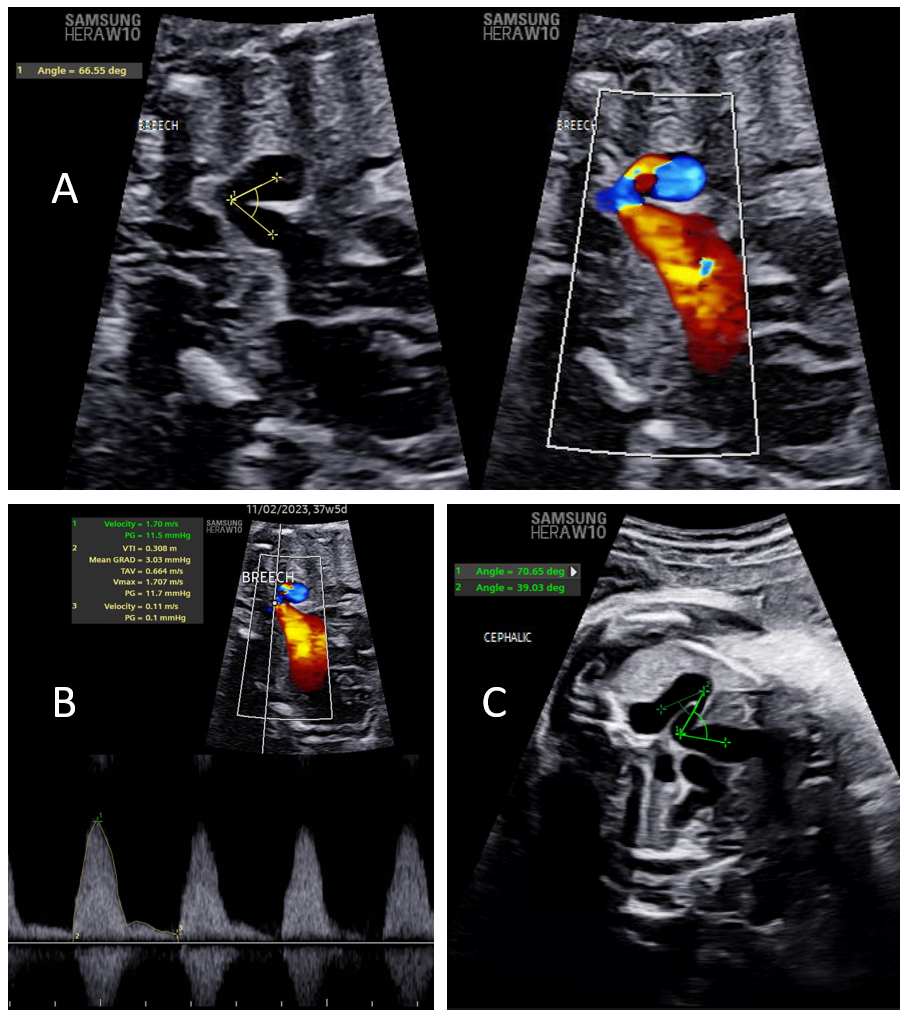

Methods: Fetuses diagnosed with tortuous DA from 01/2016 to 10/2023 and with gestational age of ≥ 32 weeks were evaluated. The degree of DA tortuosity was assessed as the minimum (sharpest) ductal angle in degrees, number of ductal bends, and ductal tortuosity grade (Table 1). Tortuosity grade was assigned as mild when a single bend in the DA had an angle > 90 degrees, moderate when a single bend in the DA had an angle < 90 degrees, and severe when there were ≥2 bends in the DA. DA flow was assessed as peak systolic flow velocity (PSV) and pulsatility index (PI) (Figure 1). Markers of RV function included degree of tricuspid regurgitation, RV size, ratio of RV to left ventricle (LV) size (RV/LV), RV function, RV hypertrophy and venous Dopplers. The association between DA tortuosity and both DA doppler flow and RV functional measures were assessed using linear regression. P-values of <0.05 were considered statistically significant.